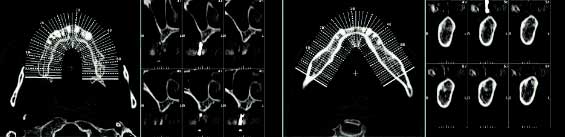

임플란트 치료를 위한 검사

임플란트 치료를 위해서는 기본적인 전신질환 유무와 같은 문진 및 구강 검사 외에도 임플란트 식립 부위의 골의 양과 질적인 평가를 하고 정확한 임플란트 식립 위치의 예측을 위해 구강내 및 구강외 방사선 사진 혹은 단층촬영(CT) 등이 필요합니다. 특히 CT 영상은 임플란트 식립부위의 골이 부족한 경우 골 이식할 부위의 정확한 해부학적인 영상을 제공함으로써 골이식술의 예후를 향상시킬 수 있습니다. 또한 임플란트 식립 위치를 가이드하는 스텐트(stent)를 미리 제작하여 CT 촬영할 때 구강내에 장착하여 촬영하면 더 정확한 임플란트 식립 위치 및 길이를 결정할 수 있습니다. 이외에도 임플란트 수술과 관련된 전신질환을 갖고 있는 환자의 경우 내과적 검사 및 혈액검사를 시행하기도 합니다.

임플란트시술을 위한 CT영상의 예 임플란트의 치료과정